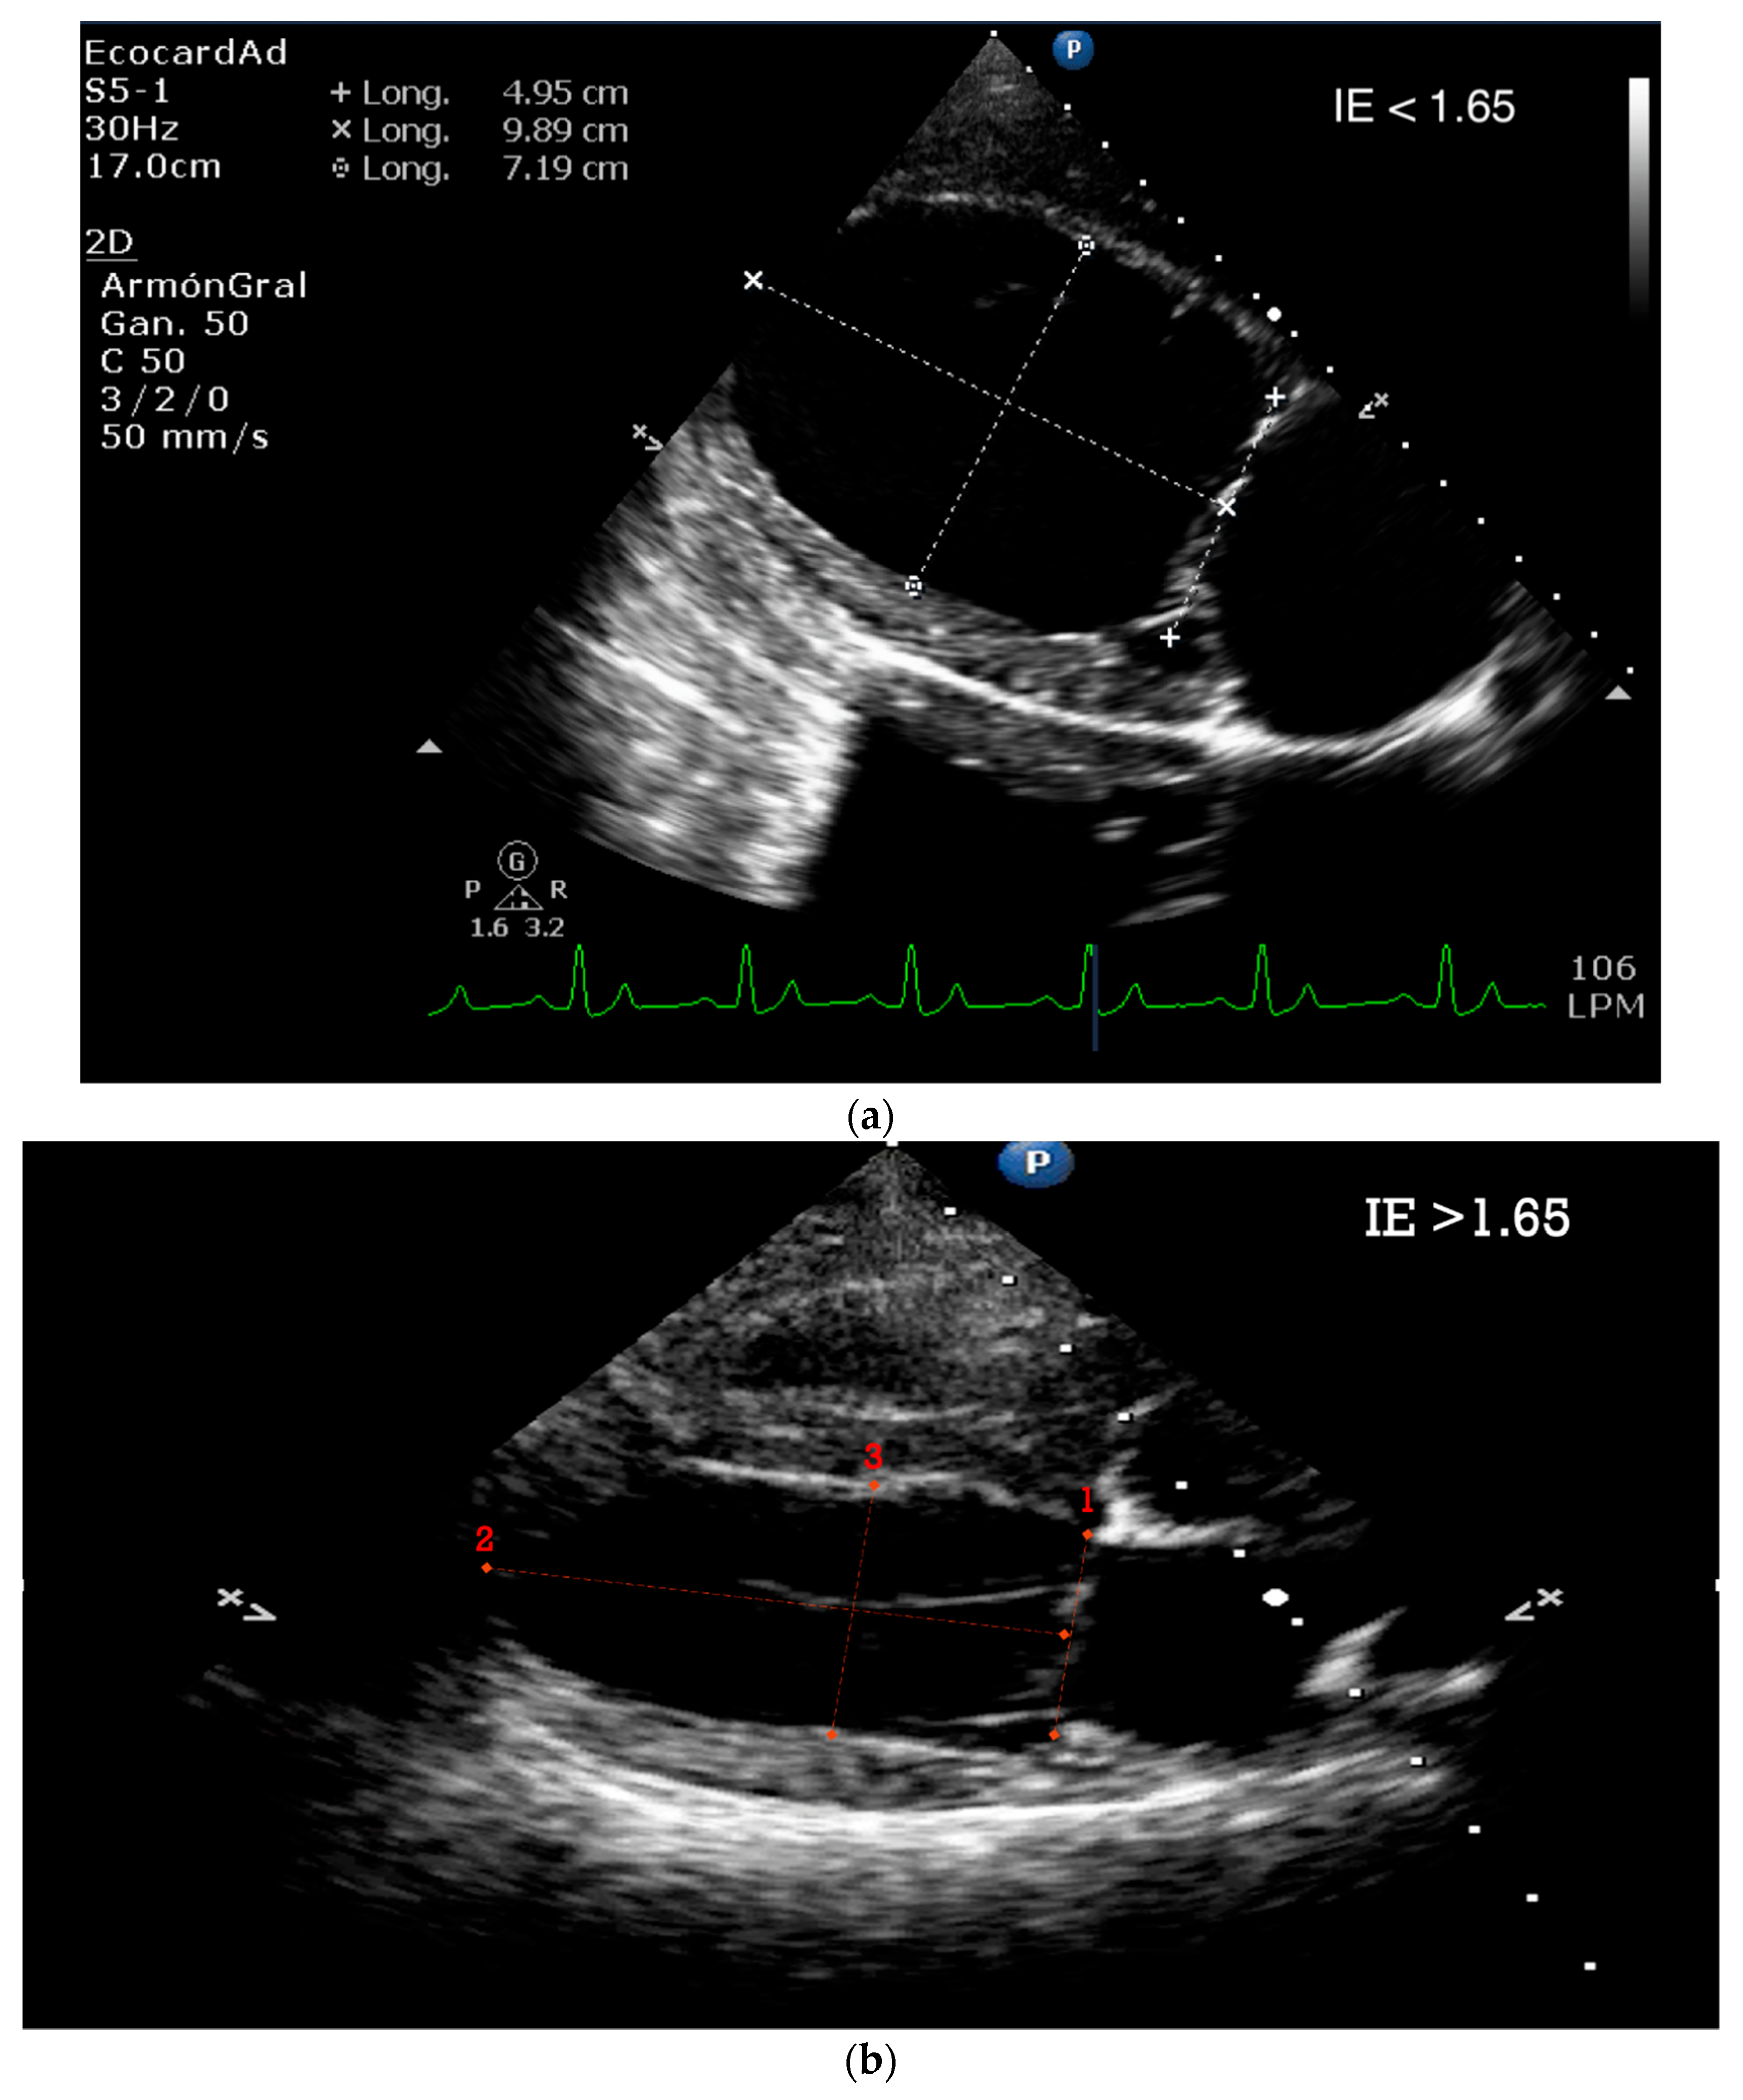

5.1.3. Sphericity Index (SI)

5.1.4. Tissue Doppler and Speckle Tracking